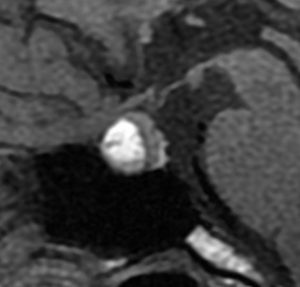

とても小さな腫瘍(微小腺腫) microadenoma

1cm以下の小さなものを微小腺腫といいます。ホルモンを異常に分泌する腫瘍は摘出する必要がありますが,そうでないものは治療の必要がありません。微小腺腫を数年観察しても増大する確率は10%くらいです。逆に,それ以上に大きなものだと,50%くらいの確率で増大します。

日本で汎用されているものでは最も解像力が高い3テスラMRIで撮影された,ガドリニウム増強像です。左側の画像では下垂体の大きさと形は正常に見えます。画像を調整すると,下垂体の内部,右端(黄色の矢印の先)に6mmくらいの小さな腺腫がみつかりました。MRIの性能がよくなったことによって数mmの小さなものも診断できるようになりました。